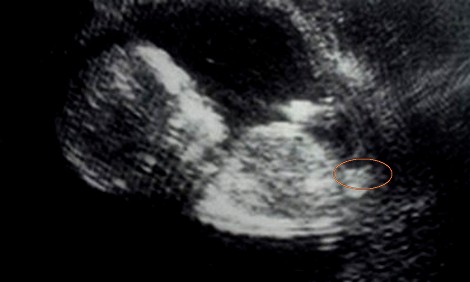

Is this a nub or still nothing for gender prediction? :nails:

The picture was from hospital yesterday at 9+5 weeks.

Is it possible that the nub already begins to rise up now? I think it looks a little bit like this? Or isnīt this the nub?:worry: